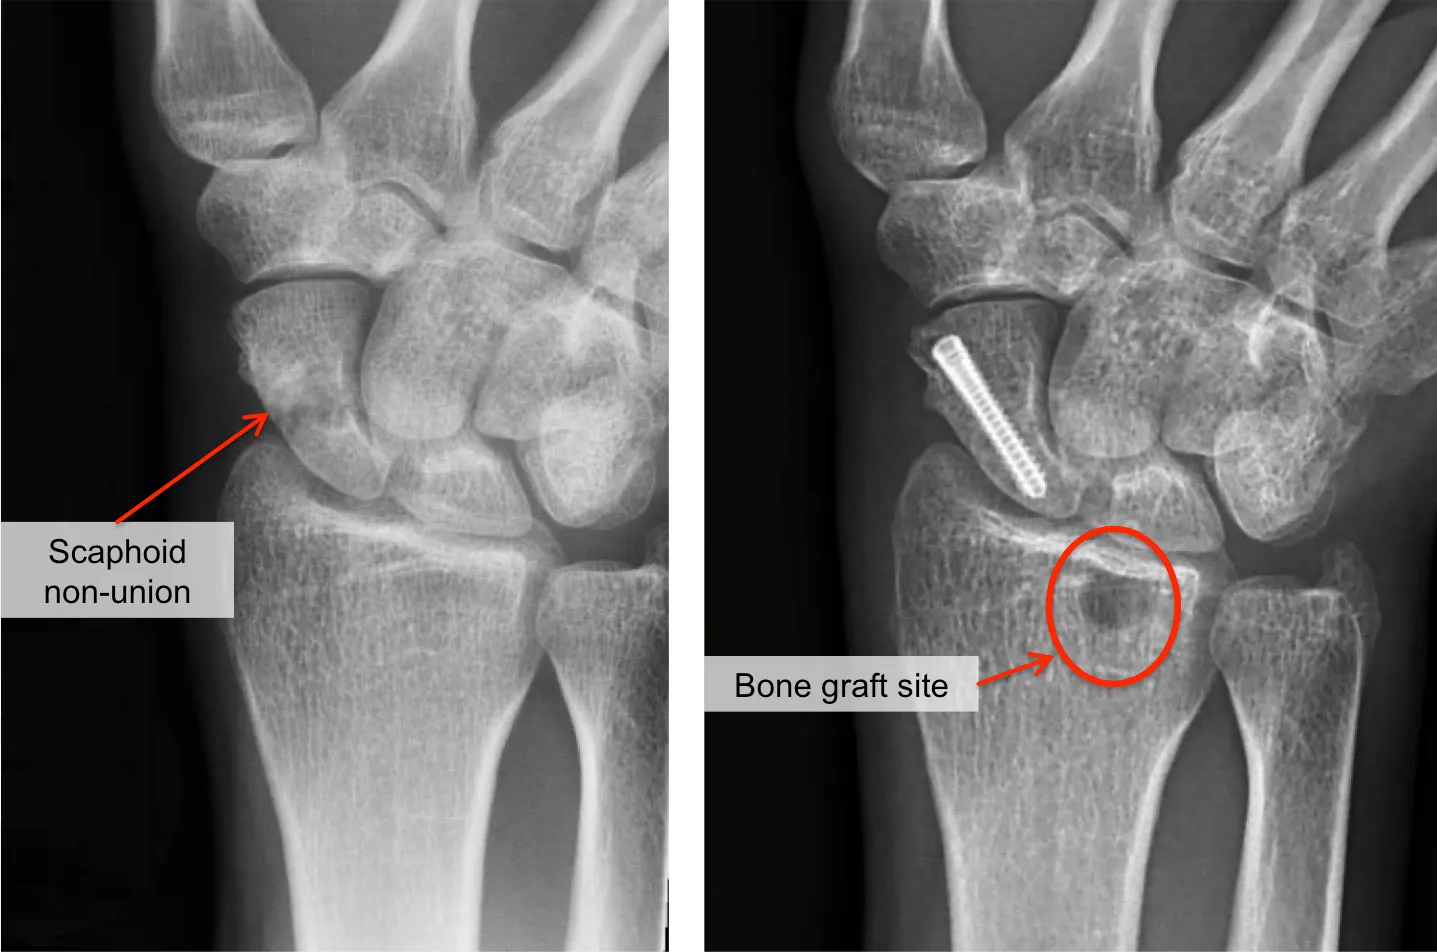

- Stap 2: Chirurgische behandeling (fixatie met bottransplantaat). In de meeste gevallen zal een operatie nodig zijn om de scaphoid non-union alsnog te laten vastgroeien:

- Open repositie en interne fixatie: De chirurg maakt een insnede bij de pols en legt het scaphoid bloot. De oude breukvlakken worden opgefrist: hij schraapt de uiteinden aan zodat er weer vers, bloederig bot ontstaat.

- Bottransplantaat (bone graft): Om de opening tussen de twee stukken scaphoid op te vullen en genezing te stimuleren, plaatst de chirurg vers botmateriaal tussen de delen. Dit bot wordt meestal elders uit je eigen lichaam gehaald, bijvoorbeeld uit de rand van het spaakbeen of uit het bekken. Soms gebruikt men een gevasculariseerd bottransplantaat: een stukje bot met een eigen bloedvat eraan, om de doorbloeding te verbeteren, vooral als het proximale deel (dichtst bij de onderam) van het scaphoid dood (necrotisch) is.

- Schroeffixatie: Nadat het bottransplantaat is geplaatst, brengt de chirurg een metalen schroef aan dwars door het scaphoid zodat de twee fragmenten stevig tegen elkaar gedrukt blijven. Vaak gebruikt men een speciale schroef die volledig in het bot verzinkt. Deze fixatie zorgt voor stabiliteit tijdens de genezing. Soms worden één of twee pinnen gebruikt in plaats van een schroef, afhankelijk van de situatie.Het inbrengen van botgreffes en schroeffixatie wordt tegenwoordig meer en meer via kijkoperatie uitgevoerd zodanig dat de bloedvoorziening van het scaphoid minder beschadigd wordt en de kans op genezing vergroot met minder verstijving nadien.

- Immobilisatie en nazorg: Na de ingreep wordt de pols gehecht en krijg je een onderarmgips of spalk die 6 tot 12 weken moet blijven. Dit geeft het bot de gelegenheid te genezen. Na ongeveer 6-8 weken worden controlefoto’s of een CT gemaakt om te kijken of er botaanbrugging is. Wanneer de arts tekenen van genezing ziet, mag de immobilisatie eraf en start geleidelijke polsrevalidatie met een handtherapeut.